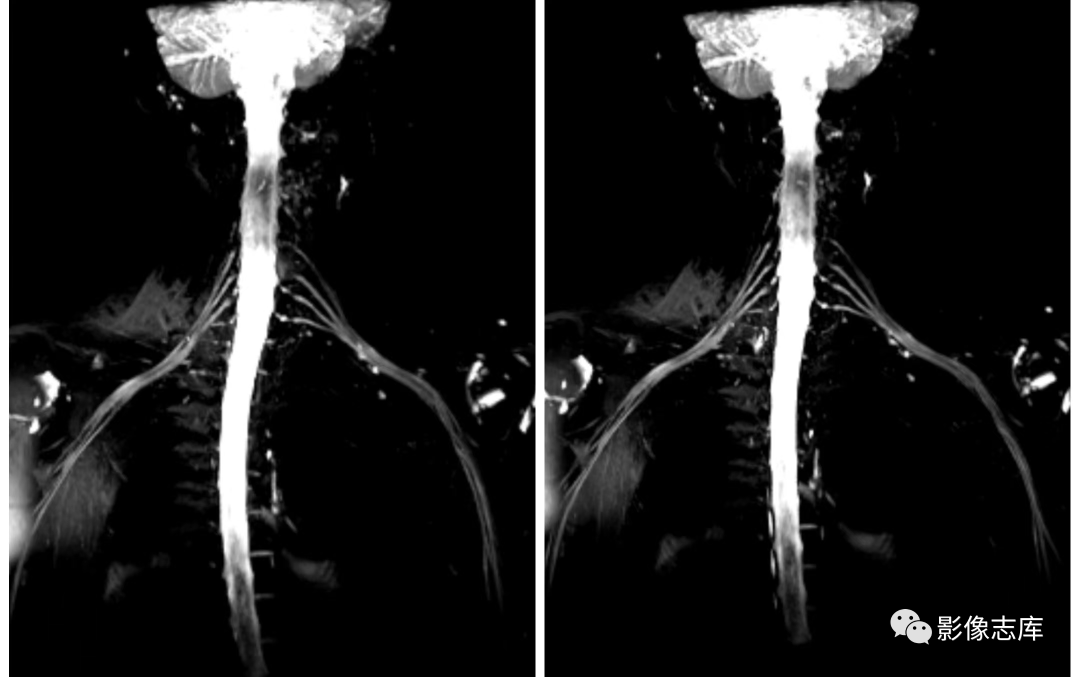

在臂丛神经扫描中,根据不同设备比如1.5和3.0T,我们选择的序列不同,总体原则就是跟扫描MRCP一样,凸显胆道系统,抑制背景组织,扫描臂丛神经也是一样的,凸显臂丛神经,抑制背景组织包括软组织、血管以及淋巴结等,因此也主要使用重T2加权成像,压脂主要选择STIR,但是有时候STIR压脂效果也不是太理想,因此还可以结合其他压脂技术,以西门子3.0T vida设备为例我们通常选择以下序列:

1.解剖结构的不规则,造成磁场均匀性下降,因此容易造成压脂失败,所以有条件的话可以使用米袋子进行填充,人为的减轻这种组织结构的不均匀;

2.由于需要大FOV的扫描,随着FOV的增大,也容易造成压脂不均匀,通常使用STIR压脂技术。

不打药和打药区别:利用重T2结合脂肪抑制STIR序列,可达到一定背景组织抑制的目的,但是血管和淋巴结很难将其抑制,为了达到这些组织不被显现,因此引入打药后的T2负性增强原理,由于微小血管和淋巴结可吸收少量对比剂,对比剂可缩短T2弛豫时间,因此通过打药后的T2加权可达到微小血管和淋巴结抑制的目的。

减轻模糊效应:SPACE序列在成像过程中使用了可变翻转角,大幅度增加回波链,减轻了T2衰减效应,避免了由于长回波链导致的模糊效应;

背景抑制:打药后进行T2 SPACE STIR cor 扫描,使背景抑制更彻底;

虽然打药后可以很好的抑制背景,提高图像对比度,但是在成像过程中,还有一些疑问就是打药后多长时间扫描才能使对比剂正好流过成像区域内的微小血管和淋巴结,这样才能保证抑制的更加彻底,我们通常在打药后3分钟左右进行扫描,但是图像有时候还是不太理想。